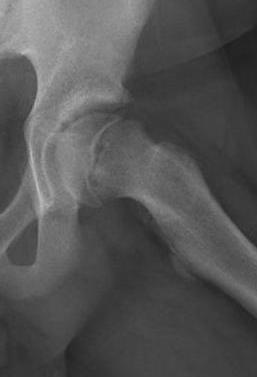

Lateral xray

Mild and moderate SCFE on left hips